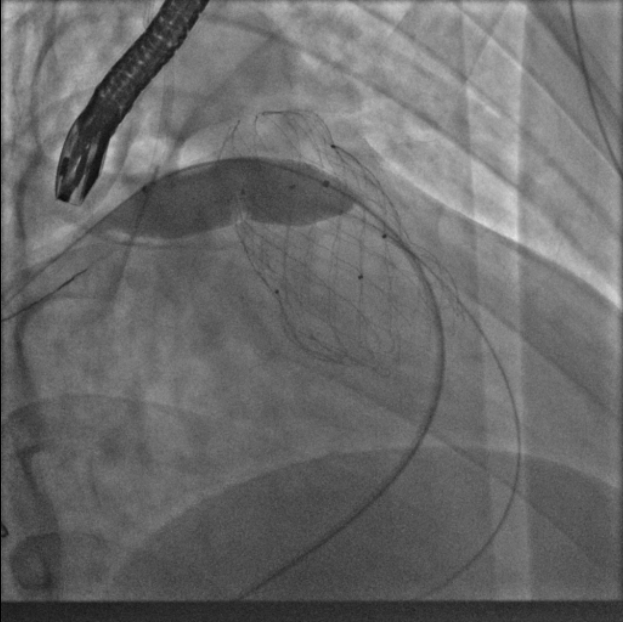

术中测量患者基础主动脉、肺动脉、右心室压力分别为111/58mmHg、31/4/13mmHg、34/1/6mmHg,通过肺动脉造影,术中测量球囊内径为32mm(见图二),选择36-25mm VENUS-P肺动脉瓣膜,在肺动脉造影指引下逐步打开瓣膜。考虑到患者肺动脉分叉较短,存在瓣膜释放后移位风险,故选择高位释放法(图三)。但释放瓣膜后造影提示右肺动脉开口局部被阻挡(图四),复测患者主肺动脉、左肺动脉、右肺动脉压力分别为57/13/25mmHg、55/12/24mmHg、27/7/14mmHg。

图三:考虑到患者肺动脉分叉较短,选择高位释放法